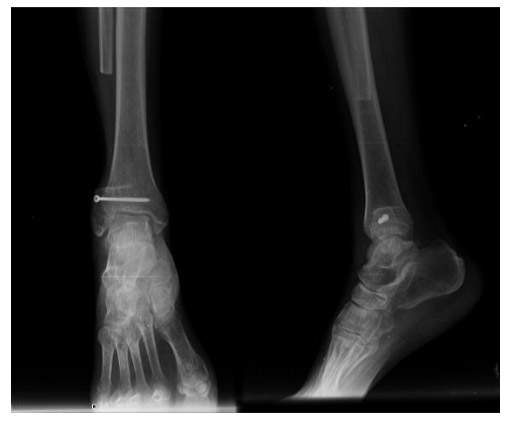

Post-surgery: The X-ray shows distal fibula resection and ankle reinforcement with a screw.